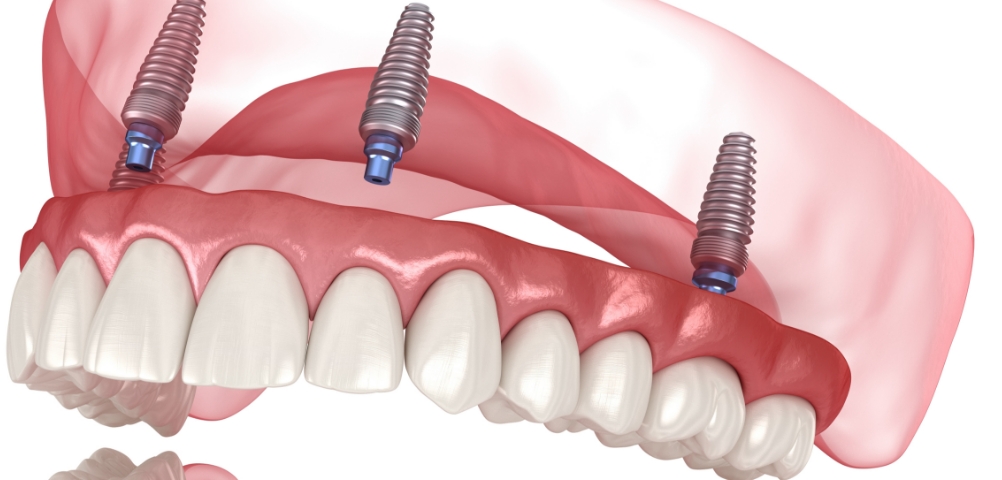

种植牙是在精准诊断与治疗计划的基础上,

通过多个步骤进行的治疗方式

会根据患者的口腔状况, 分阶段安全推进

根据患者状况,

应用个性化种植牙设计

按照预定导板,

稳定植入种植牙